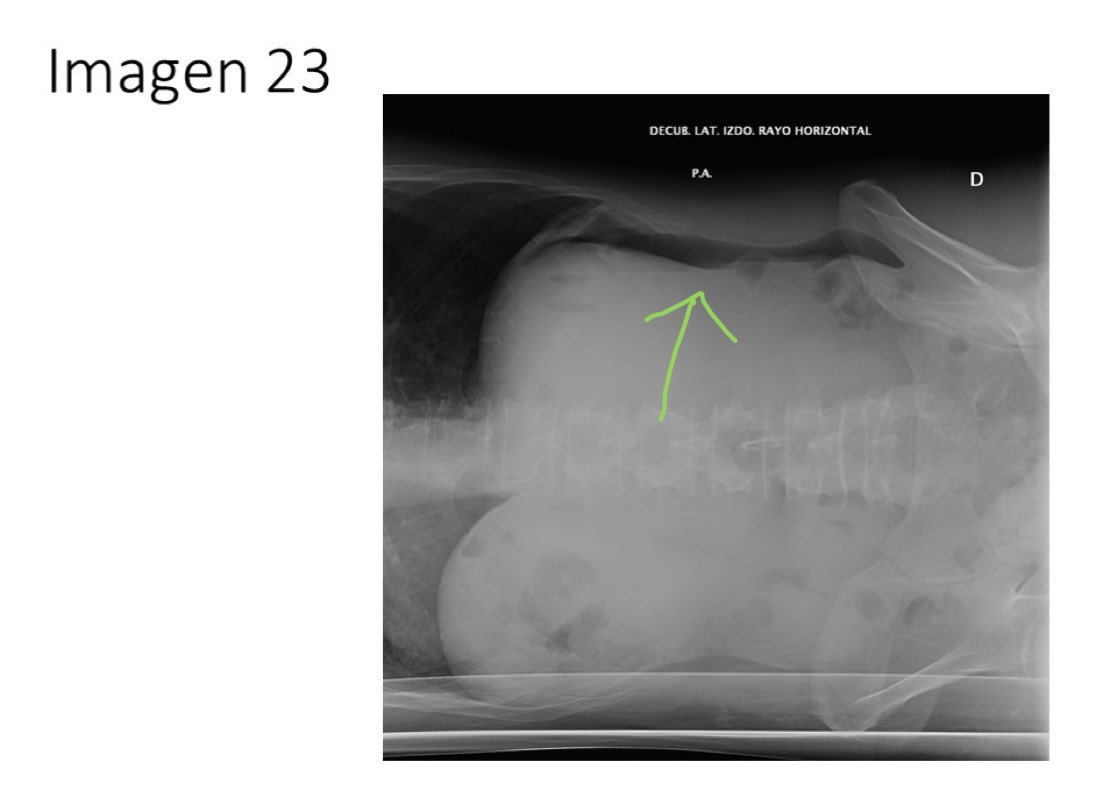

23. RX abdominal en decúbito lateral izquierdo. Es importante recordar cómo en esta proyección se desplaza el aire y podéis verlo acumulado en localización no declive. Es compatible con perforación de víscera hueca, en este caso entre las opciones, perforación gástrica.